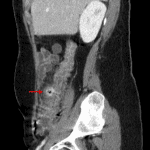

Indication: Right lower quadrant pain

- Colonic diverticulosis with mural thickening and hyperenhancement of a diverticulum arising from the proximal ascending colon with surrounding fat stranding

- Small volume free intraperitoneal fluid in the right paracolic gutter tracking into the anatomic pelvis without loculated collection or free air

- Normal appendix

- Diverticulitis

Acute uncomplicated diverticulitis involving the proximal ascending colon. No evidence of abscess of perforation.

Normal appendix.